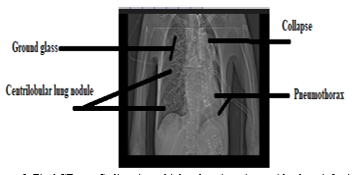

The patient was a 28-year-old man living in the village with a history of multiple sclerosis who complained of difficulty in swallowing food and persistent coughs due to food getting stuck in the throat. About a month ago, until the time of referral, food got stuck in the patient's throat when eating. For a month until the time of referral, he had numerous coughs during the day; after a month, the patient's coughs were more frequent. The patient has been unable to swallow and chew food since October 4, 2022, due to excessive phlegm and secretions. He was also observed to have increased breathing sounds, fever, chills, and sweating. The patient was referred to Ayatollah Rouhani Educational Hospital in Babol after approximately 30 days on May 11, 2022.  The patient exhibited several symptoms, including a cough with phlegm, difficulty breathing, sharp chest pain, anxiety, wheezing, headaches, and dizziness. He also experienced a punctured lung and breathlessness, and sometimes noted by a whistling sound during breathing. The patient's initial diagnosis was performed using a computerized tomography (CT) scan. Real-time PCR did not show any sign of Coronavirus disease (COVID-19). Other observations included pneumonia, extensive hydropneumothorax in the left hemithorax and complete collapse of the left lung, pneumothorax, cystic bronchiectasis in the right middle lobe, ground glass appearance or opaque glass opacity, and lymphadenopathy in the paravascular space. Following the patient's initial diagnosis in the intensive care unit (ICU), tracheostomy, nasogastric intubation, and tracheal and intrathoracic intubation were performed (Figure 1).

Figure 1. Initial CT scan findings in the patient suffering from multiple sclerosis with a lung infection.

A CT scan was conducted on the patient. A Centrilobular lung nodule with a branched appearance in the left lobe of the lung indicated aspiration pneumonia. Para-aortic lymph node and abdominal ascites were prominent. The results of the secondary CT scan in the patient showed mild pleural effusion on the left (With a significant reduction compared to the previous CT scan), pneumothorax, complete collapse, and mild peri-bronchovascular ground glass in the right lobe (Figure 2).

Figure 2. Final CT scan findings in multiple sclerosis patients with a lung infection